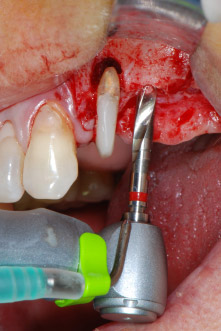

IImplant beds were prepared at sites 25 and 26 with rotary instruments, used in a contra-angle handpiece with a 20 : 1 transmission ratio with an updated powerful implant motor (Implantmed, W&H) (Fig. 8).

The final preparation next to the sinus was again carried out with a piezoelectric instrument (Piezomed, insert S2).

Prior to implant placement, and following verification of an intact Schneiderian membrane (Fig. 9), the internal sinus floor was augmented at both implant sites by means of xenogeneic bone substitute material (Bio-Oss, Geistlich Biomaterials) (Fig. 10).